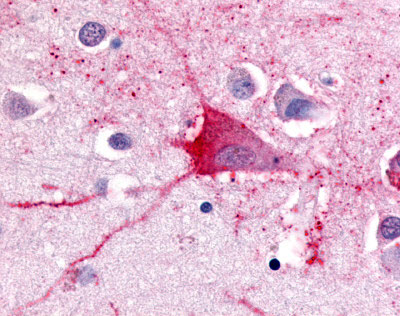

Anti-TRH Receptor antibody AMM08331G IHC of human brain, neurons and glia. |